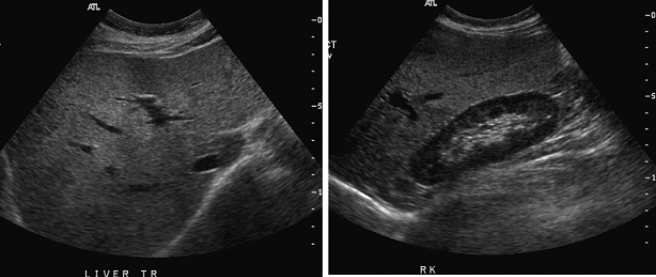

72. 附圖中左圖為腹部中線肝臟橫向掃描,右圖為肝臟右葉之縱向掃描,此肝臟最有可能是:

(A)轉移性腫瘤 (B)脂肪肝 (C)瀰漫性肝癌 (D)淋巴瘤浸潤